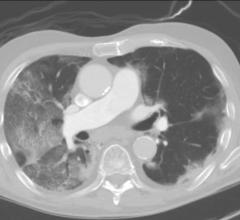

November 5, 2021 — The damage caused by Covid-19 to the lungs’ smallest blood vessels has been intricately captured…